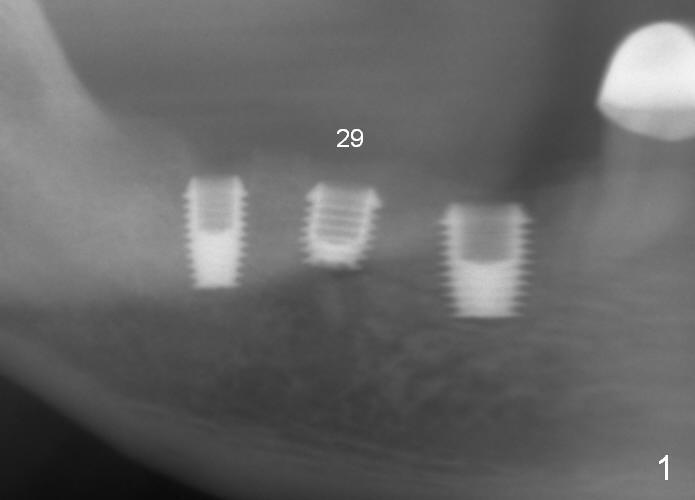

A 48-year-old man had 3 implants placed at #28-30 nearly 10 years ago (Fig.1). The implant at #29 is 4.5x6 mm because of proximity to the Mental Foramen. Bone shows gradual resorption around the implant at #29 two and 5 years postop (Fig. 2,3 >). It became loose when he accidentally bit on a piece of bone (Fig.4). A 4.5x11 (Fig.4) or 14 (Fig.2) mm tissue-level implant will be placed after Metronidazole treatment. CT will be taken tomorrow before surgery to further confirm the bone height. Since the previous implant was placed distally, the new one should be placed more mesially.